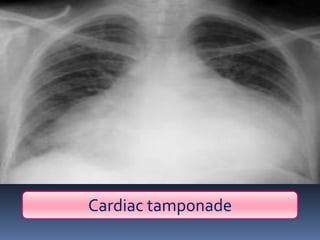

Abnormal Findings

Un equality of chest movement

Dullness on percussion

Normal air entry ,muffled heart sounds

Tachypenic, congested neck veins

Cardiac tamponade

pericardiocentesis

▪ (almost always seen with a penetrating

wound)

▪ Beck’s triad:

Hypotension

distended neck veins

Muffled heart sounds

Pulsus paradoxus